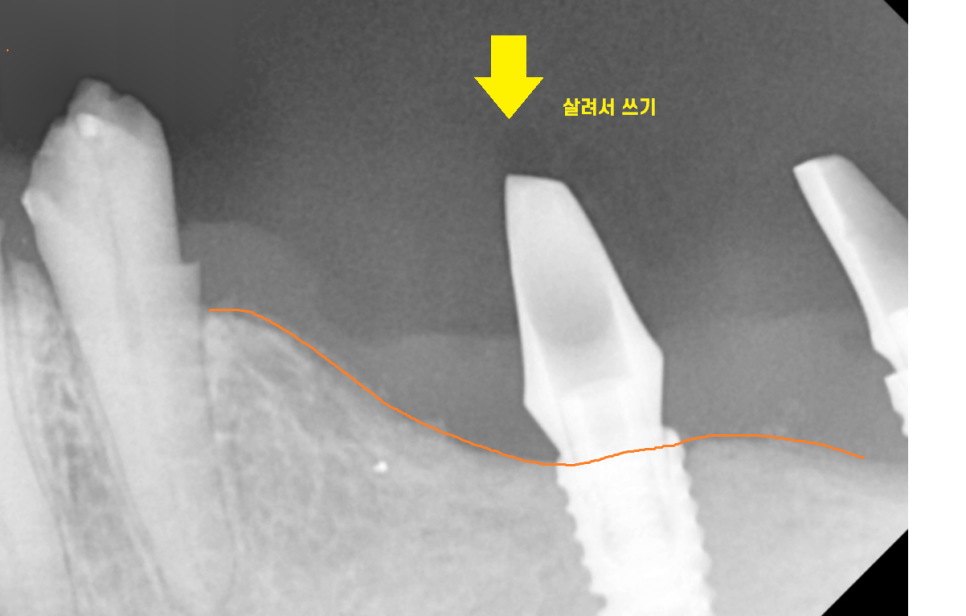

앞쪽에 있는 임플란트는 뼈가

녹지 않아서 그대로 살려서 쓰기로 결정했습니다.

수술 직후 사진입니다.

기존 임플란트가 문제가 없다면

살려서 쓸 수 있답니다~!

이가 부서진 부위를

튼튼하게 보강해 드렸으니

오래오래 쓰실 일만 남았습니다.